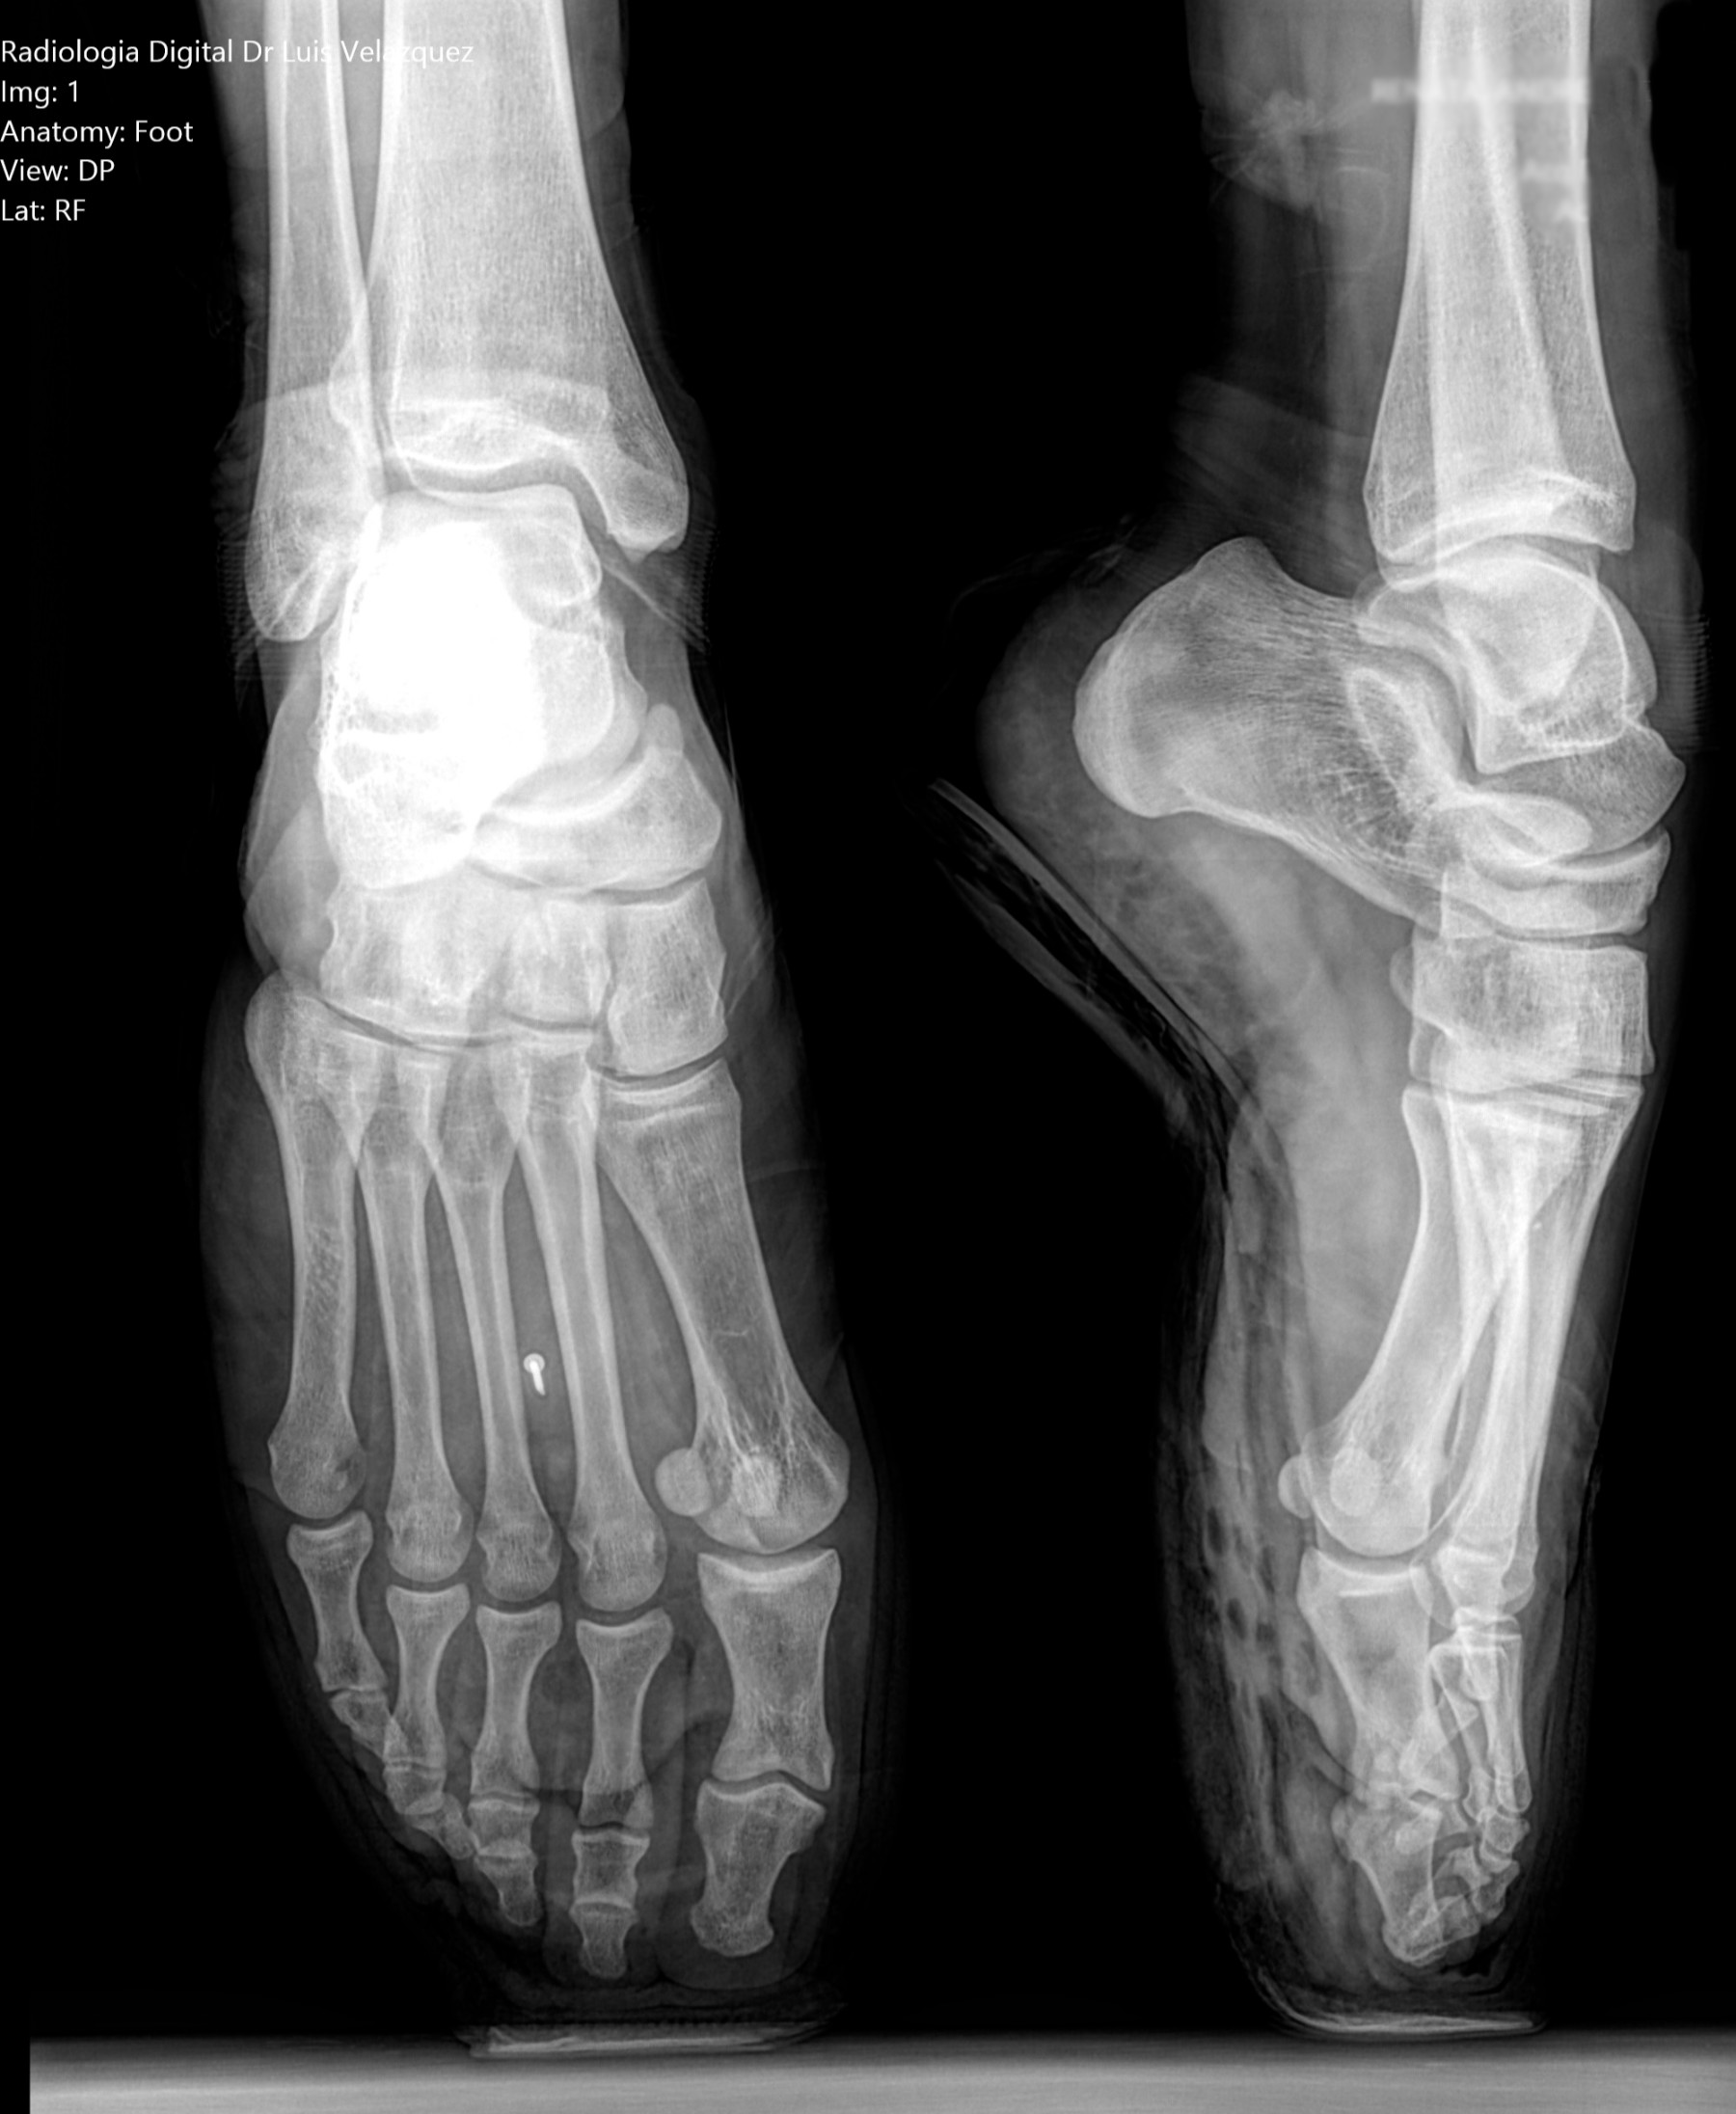

Radiología Digital como Herramienta Complementaria en el Dictamen de Bienes Muebles

Desde el descubrimiento de los rayos “X” y las placas radiográficas por Wilhelm Conrad Roentgen y su posterior difusión a través de la Asociación Físico médica de Wurzburg el 28 de diciembre de 1895, que fue la primera asociación que habló de los nuevos rayos que podían penetrar el cuerpo y fotografiar los huesos, ha habido muchos cambios tanto en la forma de obtener, procesar e incluso en la forma de visualizar, manejar y almacenar las placas radiográficas.